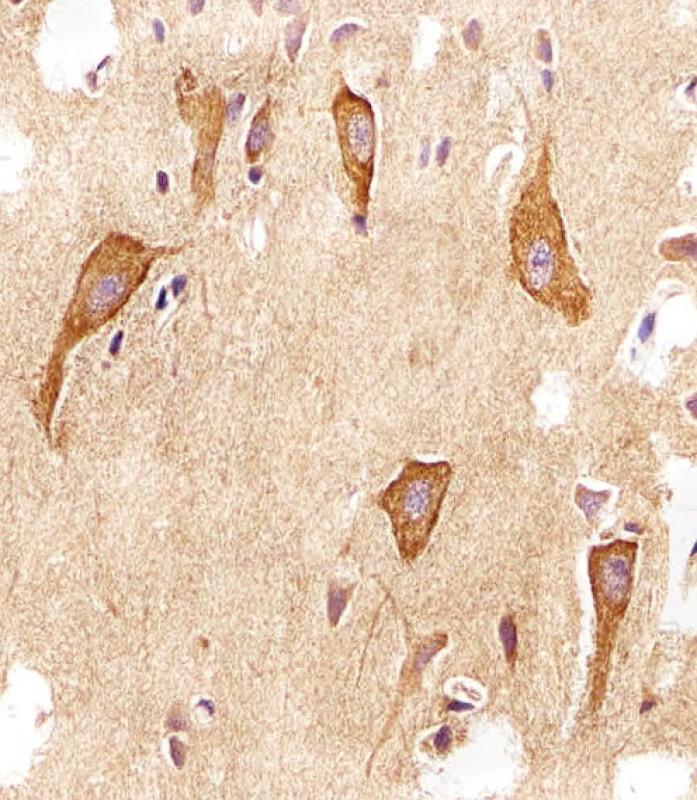

Figure 1: Immunohistochemical analysis of paraffin-embedded h brain section using VAMP8 Antibody (10-6622). VAMP8 Antibody was diluted at 1:25 dilution. A undiluted biotinylated goat polyvalent antibody was used as the secondary, followed by DAB staining.